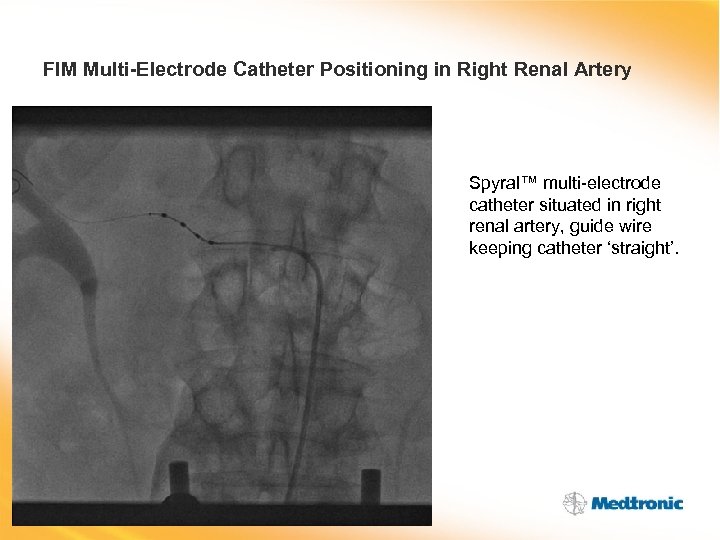

FIM Multi-Electrode Catheter Positioning in Right Renal Artery Spyral™ multi-electrode catheter situated in right renal artery, guide wire keeping catheter ‘straight’.

FIM Multi-Electrode Catheter Positioning in Right Renal Artery Spyral™ multi-electrode catheter situated in right renal artery, guide wire keeping catheter ‘straight’.